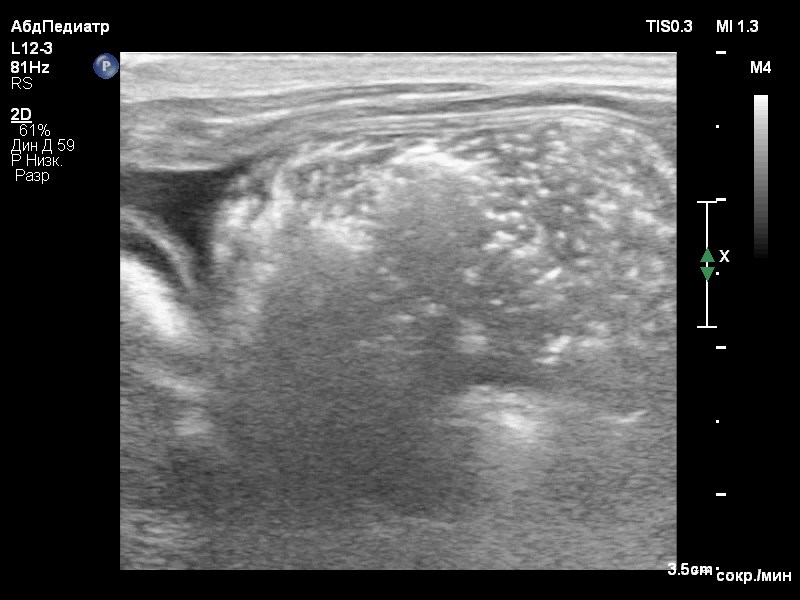

Ультразвуковое исследование органов брюшной полости выявило признаки микрогепатии, нефролитиаза, уролитиаза и асцита (скопление жидкости в брюшной полости) в небольшом количестве (до 2 мм на просвет; фото 1).